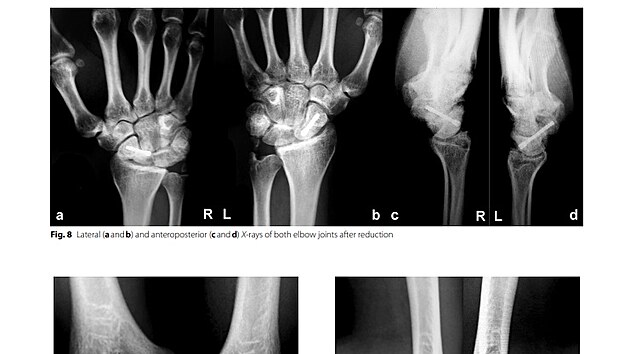

„Jedná se o raritní úraz, který nebyl dosud ve světové literatuře popsán. U pacienta, který spadl ze čtyřmetrového lešení, došlo ke zlomeninám a vykloubení obou zápěstí a vykloubení obou loketních kloubů,“ popsal operatér úrazu Jaroslav Pilný. Poraněný muž byl do nemocnice v Novém Městě na Moravě převezen z jiného zdravotnického zařízení.